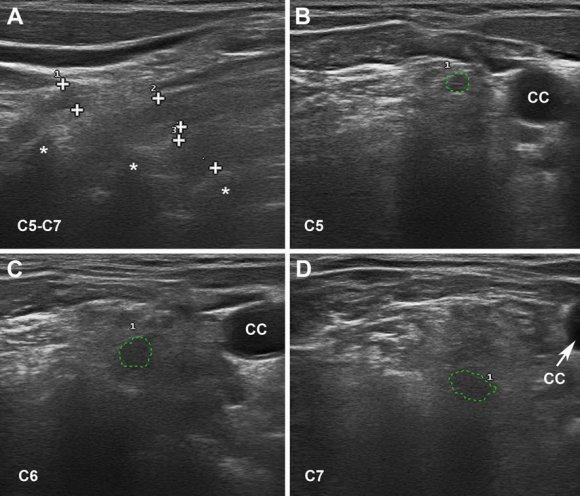

Nerve US is a routine technique in the diagnosis of peripheral nervous system disorders [37]. In our US nerve studies, main early lesions relied on ventral rami of C5-C7 nerves, these occurring equally in patients categorized as axonal GBS or AIDP [25,33]. Figure 1 illustrates sonograms of C5-C7 nerves (day 5 after onset) in a severe GBS patient, aged 80 years, who died on day 9 (case 1 in reference [33]). In our series, only a minority of patients showed abnormal peripheral nerve sonograms, essentially restricted to proximal median and ulnar nerves. In a previous early GBS study, there was significant enlargement in all measured nerves, except the sural nerves [38]. The obvious discrepancy calls for new US studies.

![Fig. 1: US of ventral rami of C5-C7 nerves in early AIDP. Taken from reference [33]. a Sagittal sonogram showing blurred boundaries of the 3 scanned cervical nerves (callipers). Asterisks indicate transverse vertebral processes. b-d Short-axis sonograms showing the cross sectional areas of each cervical nerve(dotted green tracings), whose values are as follows: C5 = 9 mm 2 (control mean 6.22; SD 2.75), C6 = 18 mm 2 (control mean 9.63; SD 4.21) and C7 = 23 mm 2 (control mean 12.29; SD 5.33). CC indicates common carotid artery](https://medicalresearchjournal.org/index.php/GJMR/article/download/2271/version/101305/7-Axonal-Degeneration-in-Guillain-Barre_html/21603/image-2.png)